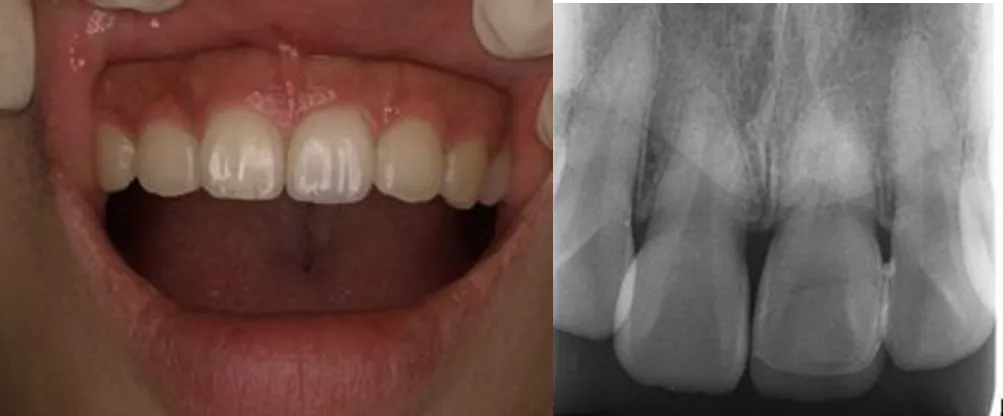

ベニア症例

ベニア術前

ベニア術後

治療内容 | ラミネートべニア |

治療期間 | 1〜2ヶ月 |

治療回数 | 4〜5回 |

リスク | 仮歯、仮づめが非常に取れやすい |

費用(税込) | ¥132,000 |

ラミネートベニア

ラミネートベニア一般的な矯正治療のように長期間時間をかけて歯を動かしたり、セラミック治療のように歯を大きく削って被せ物をしたりということは必要ないため、特に、短期間で前歯を整えたい方に向いています。 ただし、ラミネートベニアはすべての方に適用となる治療ではなく、治療を行うのがどの歯なのか、また歯列や歯がどのような状態かといったことによって治療の可否が異なります。 薄い板状のセラミックを使用するため、歯列が大きく乱れていたり、奥歯の噛み合わせが悪かったりという治療は原則的に行うことはできません。

メリット

歯を全く削らない

変色しにくい

デメリット

大きく歯並びを変えられない

適応症が限られる

治療期間 | 約1-2ヶ月間 |

---|---|

治療回数 | 2回 |

費用(税込) | 1本 ¥77,000~¥198,000程度 |